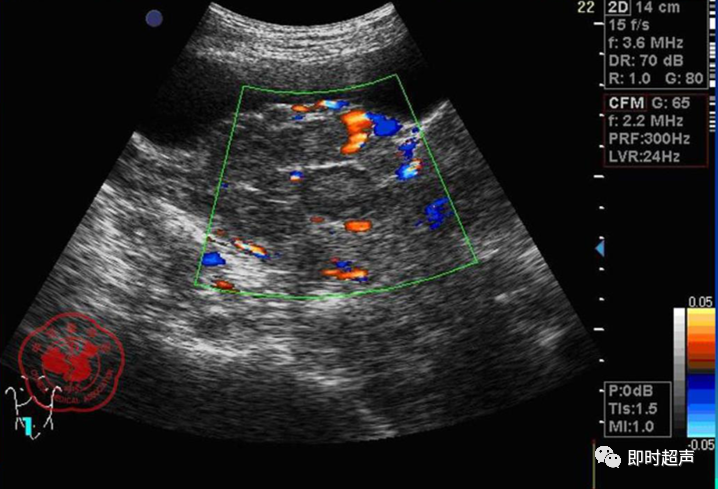

• GIST的发病机制与KIT信号通路的激活有关。• KIT是一种酪胺酸激酶跨膜受体蛋白,未经“装配”过的KIT蛋白是一种非活化的单体,参与细胞膜形成。几乎所有GIST都表达了KIT蛋白,而且大多突变的KIT基因保留了表达KIT蛋白的特性。c-kit内的突变主要见于恶性病例,特别是外显子11的点突变,还有外显子9、13和17,可以导致本质的或配体独立的c-kit激活,引发细胞的无序增殖和凋亡。这些具有功能的突变是GIST发病机理的关键,并且与肿瘤的恶性程度和预后较差相关。• GIST约75%发生于50岁以上老年人,中位年龄为58岁,无明显差异。• 可以发生在消化道从食道到肛门的任何部位,偶尔可原发于网膜、肠系膜和腹膜后,约50%发生在胃,25%发生在小肠,不足10%发生于食管、结肠及直肠。大体观察:肿块多境界清楚,类圆形,结节状,部分有假包膜。切面灰白、灰红,质韧,部分质嫩呈鱼肉状,伴有出血、坏死、囊性变。• 肿瘤组织主要由两种细胞组成,一种为长梭形细胞,细胞质丰富,嗜酸性,细胞核呈梭形或杆状;另一种为上皮样圆形或多角形细胞,细胞肥胖,胞质少。两种瘤细胞常呈束状、编织状或旋涡状排列。• 部分病例细胞异型明显,核分裂象增多,可见病理性核分裂象和瘤巨细胞。梭形细胞界不清楚,胞质丰富,淡染,轻度嗜伊红或略嗜碱,可有纤细、长梭形、短梭形或胖梭形、卵圆形,可见核仁。细胞核两端钝圆,部分病例胞质呈空泡状,位于核一端形成核端空泡胞,多呈交叉束状、旋涡状、席纹状及栅栏状排列。上皮样细胞胞浆丰富或透亮,多呈弥漫片状、束状或巢状排列。肿瘤间质可有出血、囊性变、坏死及黏液变,可见炎性细胞浸润。CD34抗原是一种115kd的糖基化蛋白,50%~80% GIST的CD34表达为阳性,CD34对鉴别GIST和典型的平滑肌瘤,神经鞘瘤还是非常有用的标记物,因后两者的CD34一般是阴性的。但CD34在诊断GIST上其特异性受到限制,一般情况下CD34多与CD117联合应用,方能提高GIST的诊断率。• 与肿瘤大小、发生部位、肿物与肠壁的关系以及肿瘤的良恶性有关。• 肿瘤较小者(直径小于2cm)常无症状,往往在体检和其它手术时无意中发现。• 肿瘤发生于胃肠道腔内时大多表现为呕吐、腹痛及消化道出血,而发生于胃肠道腔外的则主要表现为腹部包块。• 最常见的临床症状是中上腹部不适、腹部肿块及便血。• 对于临床发现的消化道(包括肠系膜、网膜、后腹膜)实体肿瘤,在排除其他常见肿瘤后,才考虑GIST。目前,诊断GIST有三条标准:③肿瘤组织具有梭形细胞和上皮样细胞两种基本细胞成分的病理学特征。这是诊断GIST金标准。CD117阳性者或CD117阴性而CD34阳性者,且伴平滑肌和神经双向分化或无分化者,可诊断为GISTs;以Desmin和SMA强阳性,而CD117阴性诊断为平滑肌肿瘤;以S-100阳性,CD117、Desmin、SMA均阴性诊断为神经鞘瘤。• GISTs的分型与组织学良恶性的关系:研究证实GISTs非单一分化的肿瘤,具有多向分化。• 当前GISTs的良性、交界性和恶性判断标准多参照Amin等提出的标准:②交界性:核分裂<5/50HPF,但肿瘤>5cm;• 另外研究显示,平滑肌型大多数为良性,少数为交界性和恶性,神经源型为恶性,双向分化亚型和未分化型为交界性和恶性,提示GISTs的分化型与其良恶性之间有一定关系。• 胃间质瘤早期多局部侵犯,后期出现肝转移和腹腔内种植,小肠间质瘤早期即可出现转移• 主要有超声扫描(检出率30%左右)、纤维内镜、超声内镜、CT、MRI、普通X• 线检查(胃肠钡餐造影、小肠插管气钡双重造影)、选择性血管造影检查等。• 不同部位的GIST,各种检查方法的敏感性不同。以CT检查为佳,尤其是螺旋CT,分辨率最高,可以三维重建,直接显示肿瘤大小、形态、密度、内部结构、边界,对邻近组织的侵犯也看得很清楚,同时还可观察其他部位的转移灶,有利于分期、鉴别与诊断。• MRI具有多轴成像及反映肿瘤内部成分的优点,尤其是动态扫描及各种新的扫描系列的出现更使其可以普及应用。• DSA检查对于GIST,特别是有消化道出血的患者更有价值。• 上述影像学检查表现并非特异性,与胃肠道平滑肌肿瘤、神经源性肿瘤鉴别困难。明确诊断要依赖病理免疫组化等手段。• 超声图像特征 肿物体积较小者(直径< 5. 0 cm )多为实性病变, 呈类圆形, 边界清晰, 内部回声多为较均匀的低回声。• 肿物体积较大者(直径> 5. 0 cm ) 多为混合性病变,呈不规则圆形或分叶状, 多数边界尚清晰, 以实性为主的病变内部为不均质中低回声伴不规则液性区及斑点状强回声; 以囊性为主的病变囊壁较厚,有分隔, 部分囊腔内可见点状、团状低回声。CDFI显示肿物实质回声内血流均较丰富。病例1:患者男, 62岁。自扪腹部包块2月余,包块增大20天就诊。查体:腹部平坦,无腹壁静脉曲张,无胃肠型及蠕动波,腹肌软,剑突下5cm处及左肋缘下可触及一质韧包块,大小约15*12cm,活动度差,边界尚清,包块深压痛,全腹无反跳痛。化验检查AFP:3.66(1.09-8.04)ng/ml,CEA:2.85(0-5)ng/ml。体格检查:一般情况良好,全腹软、平坦,腹部无压痛。超声检查:患者仰卧位时左上腹于胰尾前方可见一大小约6. 1 cm ×5. 8 cm ×5. 3 cm实性均质低回声,形态规则,包膜完整,边界清晰,活动度大;右侧卧时,肿块移至胰头右前方(图1) ;于其内探及丰富血流信号。体格检查:一般情况良好,腹丰满,上腹部有轻压痛,未扪及明显肿块。超声检查:患者仰卧位时左上腹于胰尾前方、脾门处可见一大小约10. 0 cm×8. 8 cm×7. 6 cm 实性低回声(图2) ,形态规则,包膜完整,边界清晰,肿块活动度大;右侧卧时,肿块移至左肝下间隙,回声尚均质;于其内探及较丰富血流信号(图3) 。图3 腹腔低回声肿块位于左肝下间隙,于低回声肿块内探及较丰富血流信号向壁外生长的胃肠道间质瘤, st为胃腔,箭头所指为胃壁, T为向外生的肿瘤• 胃间质瘤的定位准确率要高于十二指肠及小肠间质瘤,这主要是因为胃的解剖位置相对固定,且通过饮水使胃腔充盈,可清晰的显示胃壁的各层结构及肿块与胃壁的关系。肿块多表现为粘膜下、肌层或浆膜下低至中等回声团块,可向腔内、腔外或腔内外生长。但当肿瘤较大或浸润周围脏器时,超声定位仍有困难, 因此,超声如发现上腹部肿块且怀疑来源于胃者,应尽可能嘱其饮水充盈胃腔,并多角度、多切面观察肿块与周围脏器的关系,以提高定位的准确性。• 十二指肠间质瘤的定位亦较准确,但降部的外生性肿块常与胰头粘连而误诊为胰腺肿瘤回声均匀且位置较深的间质瘤亦可能误为胰头周围淋巴结。• 空、回肠间质瘤常因肿块较大,多发,位置不固定而难以定位,往往误诊为腹、盆腔或腹膜后肿瘤,超声检查如发现肿块局部肠壁增厚,肿块与肠道随呼吸同步运动时可作出定位诊断。• GIST的声像图表现有助于其良、恶性的鉴别:良性肿瘤多体积较小,圆形或椭圆形,回声均匀,边界清晰。恶性肿瘤多较大,呈不规则分叶状,回声不均匀,内部易出血、坏死、囊变。• 肿瘤长径与肿瘤内部是否出现无回声区在良、恶性病变之间的差异有统计学意义,是判断良恶性的有效征象。• 如以肿瘤长径>5cm为诊断恶性标准,其敏感性、特异性及准确性均较理想。超声可为临床提供胃肠道间质瘤的部位、大小、边界、回声等较多有用信息,一部分病例可作出定位、定性诊断,并可在术后或复发患者药物治疗期间对其进行动态观察;CDFI方便快捷、无需造影剂即可对间质瘤周边及内部血流进行观察,可为临床医师提供肿瘤血供情况。但未发现腹腔或肝脏转移时,超声判断胃肠道间质瘤性质有一定难度。• 目前临床上对GISTs的治疗效果并不十分满意。治疗仍以手术为主,对无法手术切除或已有转移的GISTs患者进行甲磺酸伊马替尼化疗。• 手术方式取决于肿瘤大小、部位和术中冰冻切片结果等。• 发生在胃的间质瘤,可首选胃大部切除术;发生在十二指肠的间质瘤可行保留胰头的十二指肠切除术或胰十二指肠切除术;发生在小肠的间质瘤可行肿瘤肠段切除术;发生于结肠的间质瘤可行左半或右半结肠切除术;发生于直肠的间质瘤可行肿瘤局部切除术。一般情况下无需淋巴结清扫。• 术后随访监测,复发者单个病灶可考虑手术切除;多发或转移特征者应试行甲磺酸伊马替尼化疗,并监测肿瘤大小及数目的改变。• 随着分子靶点药物进入肿瘤临床,一种小分子化合物———酪胺酸激酶受体抑制剂,美国称为Gleevec,欧洲叫做Glivec(格列卫),在治疗GIST和慢性粒细胞白血病方面有其独特的作用。已知细胞膜表面上皮生长因子受体酪胺酸激酶抑制剂大致分为两大类:一类是小分子化合物;另一类是特异性抗体。利用抑制酪胺酸激酶的活性,对处于增殖期状态的病变具有治疗的作用。Glivec在体外、体内和细胞水平都可强烈抑制酪胺酸激酶的活性,是干细胞因子(SDCF)受体KIT的强抑制剂。• Glivec推荐用量为400mg(4片),每日一次, 3个月为一疗程。如服3个月后无效可加至600mg/d~800mg/d(6~8片)[18];若仍无效果不再增量应停止治疗。• Glivec治疗进展转移的GIST总有效率为50%左右,比传统化疗有效率高十倍以上;肿瘤生长控制率达80%以上,起效最快在服药后24h之内,使症状改善如疼痛缓解;平均起效时间为13周(约3个月)。患者体力状况改善是又一突出效果。2/3患者治疗后无症状可如健康人生活工作。• Brainard等研究发现间质瘤预后差的前两位因素为肿瘤大小和核分裂象,故对于间质瘤直径>5cm和核分裂象>5/50HPF的患者应给予口服Glivec。最近,Liu报道口服Glivec治疗可使85%患者的病情得到控制。